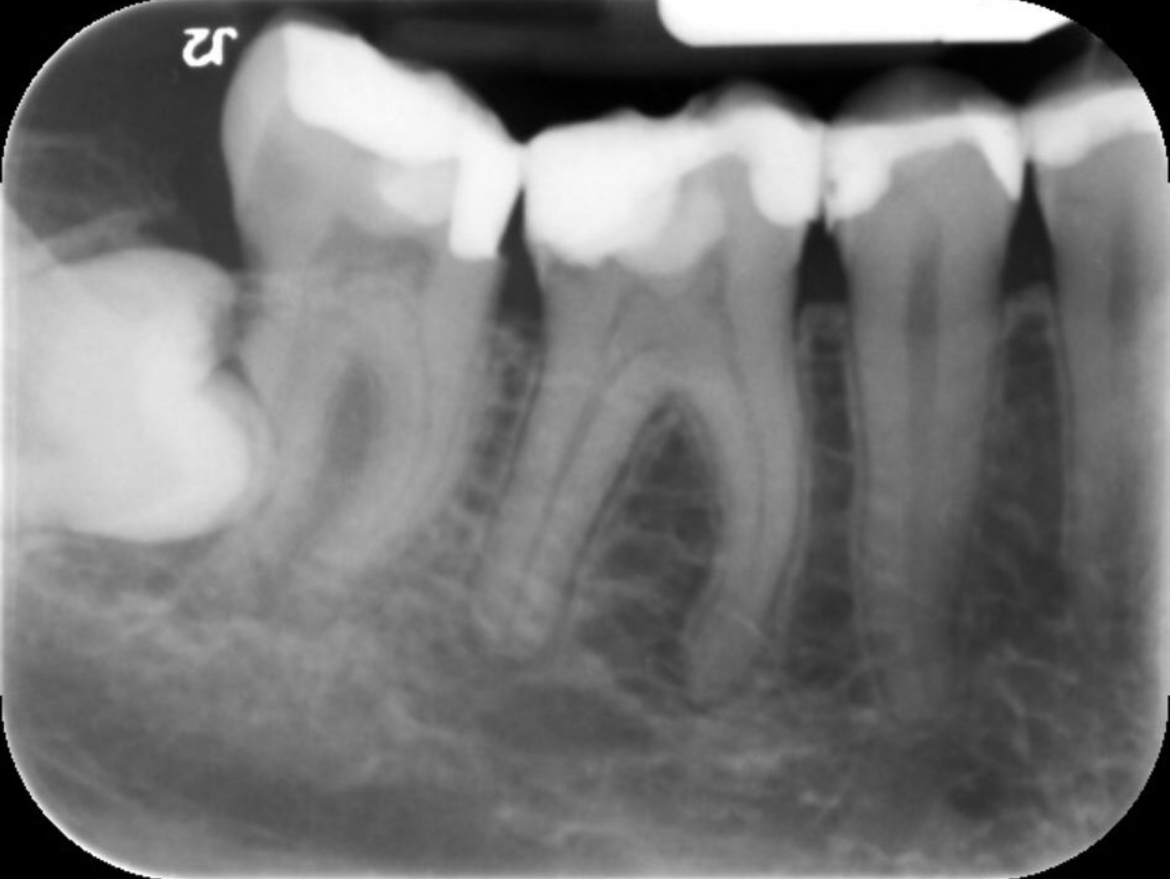

Wie kan mij helpen. Na lang uitstellen heb ik toch maar een afspraak gemaakt bij de kaakchirurg ingepland om mijn verstandskies eruit te halen die dwars ligt. (23 februari) De kiest daarnaast blijft staan en in de andere kies die daar naast staat zou een ontsteking zitten in de wortelpunt. Ik schrok heel erg van de kosten dus twijfel nu wat te doen. Of een wortelkanaalbehandeling of door de vele vullingen die al in deze tand zitten deze ook maar te trekken. Ik ben erg onzeker over mijn gebit door alle vullingen die ik heb in met name de kiezen. Aan de andere kant van mijn gebit is namelijk ook al een kies getrokken omdat deze gewoon heel zwak was en constant afbrak.

Ik hoop dat ik nog wel even met mijn tanden kan doen. Wat vind je op dit moment van de foto?

Je zou dus wel een wortelkanaalbehandeling doen ipv trekken (de eerste kies)

Zie je een grote ontsteking? Of kan dit nog behandeld worden met een antibiotica kuur.

Verstand kies verwijderen, wkb 46 ( eerste grote kies flinke ontsteking niet met AB kuur goed te krijgen) later kroon ( als u kiest voor behoud met vaste voorzieningen).....

Ik ben vanmorgen naar de kaakchirurg geweest. We moesten een nieuwe afspraak inplannen ivm de kies die in het kaakbot ligt. Graag uw mening over kies 46 aan dezelfde kant.

Kaakchirurg vind het lastig beoordelen en de tandarts ook. Ik heb geen pijn maar de kies is wel zwak en er zit een ontsteking (weet niet in welke staat de ontsteking is) kaakchirurg denkt dat trekken beter is uiteindelijk. Tandarts zegt wortelkanaalbehandeling proberen. Ik ben erg verdrietig over de situatie

U ziet wat er gebeurt als een kies getrokken wordt en niet wordt vervangen ( zie hoe links onder, 37, uitgegroeid is).

Er zijn ontstekingen aan de 46/ 33/ 34/ mogelijk 25 en gaatjes in de 15/ 14???/24??/25??/45?? moeilijk te zien op deze foto daar zou extra kleine foto's voor gemaakt moeten worden... Zwaar gevulde kiezen waar geen kronen op zijn gemaakt. Problemen met uw bot niveau ( voortanden boven). Roker??. Als u geen financiele middelen heeft zou ik in dit geval een frame prothese overwegen.

Uheeft een x-foto mee gestuurd. Daar heb ik op gereageerd met wat ik zie. Omdat ik de behandel strategie voor de toekomst niet weet heb ik een voorzet gegeven v een v d mogelijkheden (frame) en wat daarvoor nodig is, de zichtbare valkuilen.. Een frame indien de 46 getrokken wordt en geen WKB (duidelijk te zien op de eerste x-foto) gekozen wordt. Met dat advies kunt u doen wat u wilt.